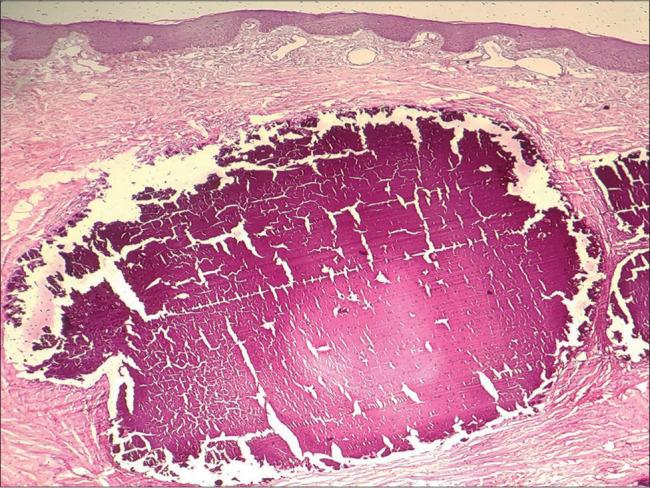

A subcutaneous firm nodule on scrotal skin: Cytological considerations.

Cytojournal. 2022 Jul 16;19:46. doi: 10.25259/Cytojournal_27_2021. eCollection 2022.

摘要

Idiopathic Scrotal Calcinosis: A Case Report and Review of Postoperative Outcomes.特发性阴囊钙化症:一例报告及术后结果回顾

Idiopathic scrotal calcinosis diagnosed by fine needle aspiration cytology-Report of a rare case.经细针穿刺细胞学诊断的特发性阴囊钙质沉着症——1例罕见病例报告

Idiopathic scrotal calcinosis: Is cytological diagnosis enough?特发性阴囊钙化症:细胞学诊断足够吗?

Cytologic features of idiopathic scrotal calcinosis.特发性阴囊钙化症的细胞学特征。